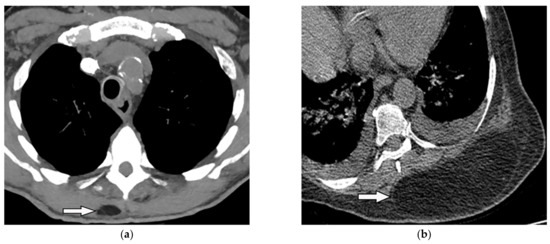

Its radiologic appearance varies from purely non-expansile osteolytic to multicystic mass with bony expansion. CT may reveal extrapleural mass with a well-circumscribed margin and “soap bubble” appearance in advanced cases (Figure 6a,b). MRI shows T1-hypointensity and T2-hyperintensity (Figure 6c) [16,25]. SBP tends to show metabolic activity on 18F-FDG PET/CT, which seems to be a risk of multiple myeloma transformation (Figure 6d,e) [26].

Figure 6.

A 63-year-old woman with incidentally detected mass at the left posteromedial chest wall. Axial chest CT with mediastinal (a) and bone (b) window show a well-defined expansile mass (arrow) with the destruction of the adjacent rib. There is no internal calcification. No neural foraminal extension was seen (not shown). (c) T2W images of another patient with the same pathology show mildly expansile marrow replacing lesions at proximal posterior rib with high T2 signal intensity without cortical disruption or soft tissue mass. Increased metabolic activity is present on 18F-FDG PET/CT (d) Axial and (e) sagittal (arrow).